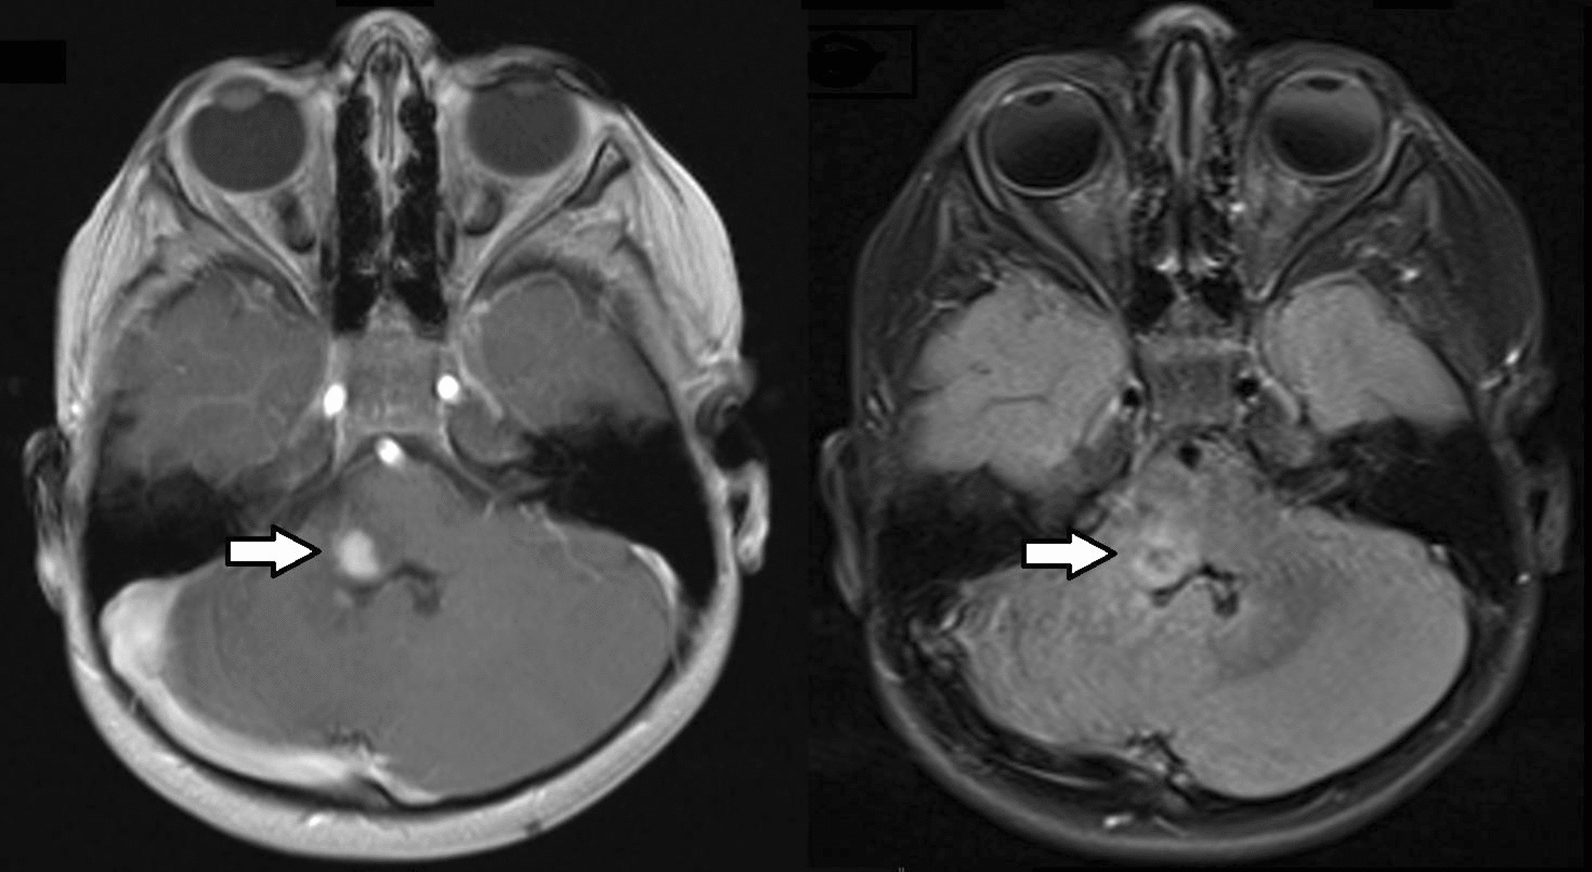

Fig. 1.

T1-weighted post-contrast (left panel) and T2/FLAIR-weighted (right panel) magnetic resonance images revealing a partially contrast-enhancing intra-parenchymal right medullary tumor (arrows). The tumor involved the right lateral aspect of the inferior pons, brachium pontis and ventral cerebellum